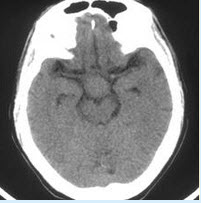

患者男性,54岁,因“视力进行性下降伴恶心、呕吐2个月余”于2011年03月12日16∶22门诊入院。入院后问病史时其家属代诉患者性功能下降2年,最近1周思维混乱、胡言乱语、嗜睡,入院时携带外院CT检查见下图。

患者男性,54岁,因“视力进行性下降伴恶心、呕吐2个月余”于2011年03月12

[多选题] 患者男性,54岁,因“视力进行性下降伴恶心、呕吐2个月余”于2011年03月12日16∶22门诊入院。入院后问病史时其家属代诉患者性功能下降2年,最近1周思维混乱、胡言乱语、嗜睡,入院时携带外院CT检查见下图。提示:患者完善术前检查后手术切除肿瘤,术后病理提示颅咽管瘤。关于该患者,叙述正确的是()A . 该患者肿瘤可能为鳞状乳头型颅咽管瘤B . 患者的思维混乱、胡言乱语等精神异常与肿瘤本身无关C . 术后尿崩症可能是一过性,也可能是永久D . 术后水、电解质紊乱的诊断及处理是围术期治疗的关键E

患者男性,54岁,因“视力进行性下降伴恶心、呕吐2个月余”于2011年03月12日16∶22门诊入院。入院后问病史时其家属代诉患者性功能下降2年,最近1周思维混乱、胡言乱语、嗜睡,入院时携带外院CT检

[多选题]患者男性,54岁,因“视力进行性下降伴恶心、呕吐2个月余”于2011年03月12日16∶22门诊入院。入院后问病史时其家属代诉患者性功能下降2年,最近

患者男性,54岁,因“视力进行性下降伴恶心、呕吐2个月余”于2011年03月12日16∶22门诊入院。入院后问病史时其家属代诉患者性功能下降2年,最近1周思维混乱、胡言乱语、嗜睡,入院时携带外院CT检

[多选题]患者男性,54岁,因“视力进行性下降伴恶心、呕吐2个月余”于2011年03月12日16∶22门诊入院。入院后问病史时其家属代诉患者性功能下降2年,最近

患者男性,54岁,因“视力进行性下降伴恶心、呕吐2个月余”于2011年03月12日16∶22门诊入院。入院后问病史时其家属代诉患者性功能下降2年,最近1周思维混乱、胡言乱语、嗜睡,入院时携带外院CT检

[多选题]患者男性,54岁,因“视力进行性下降伴恶心、呕吐2个月余”于2011年03月12日16∶22门诊入院。入院后问病史时其家属代诉患者性功能下降2年,最近